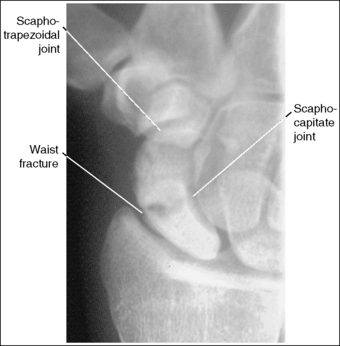

• Three areas of the scaphoid may be fractured: the waist, which sustains approximately 70% of the fractures; the distal end, which sustains 20% of the fractures; and the proximal end, which sustains 10% (Figure 4-47). Because scaphoid fractures can be at different locations on the scaphoid, precise positioning and central ray angulation are essential to obtain the optimum demonstration of this bone.

• Demonstrating fractures of distal and proximal scaphoid. When a fracture is suspected because of persistent pain and obliteration of the fat stripe but has not been demonstrated on routine images, it may be necessary to use different angles to position the central ray parallel with these fractures sites (Figure 4-48). A decrease of 5 to 10 degrees in central ray angulation better demonstrates the proximal scaphoid. Compare Figures 4-49 and 4-50. These PA axial projections demonstrate a proximal fracture. Figure 4-49 was taken with the typical 15-degree proximal angle, and Figure 4-50 was taken with a 5-degree proximal angle. Note the increase in fracture line visualization in Figure 4-50. Increase the central ray angle by 5 to 10 degrees, with a maximum of 25 degrees, to demonstrate a distal scaphoid fracture best (Figure 4-51). Angulations more than 25 degrees project the proximal second metacarpal onto the distal scaphoid, obscuring the area of interest (see Image 57).

Figure 4-49 PA axial (scaphoid) projection taken with a 15-degree proximal central ray angle demonstrating a proximal scaphoid fracture.

Figure 4-50 PA axial (scaphoid) projection taken with a 5-degree proximal central ray angle demonstrating a proximal scaphoid fracture.

This image demonstrates a scaphoid waist fracture. The scaphotrapezium, scaphotrapezoidal, and CM joint spaces are closed. The hand and fingers were not positioned flat against the IR. The scaphocapitate and radioscaphoid joints are closed, indicating that the degree of obliquity was inadequate and the proximal forearm was slightly depressed, respectively.